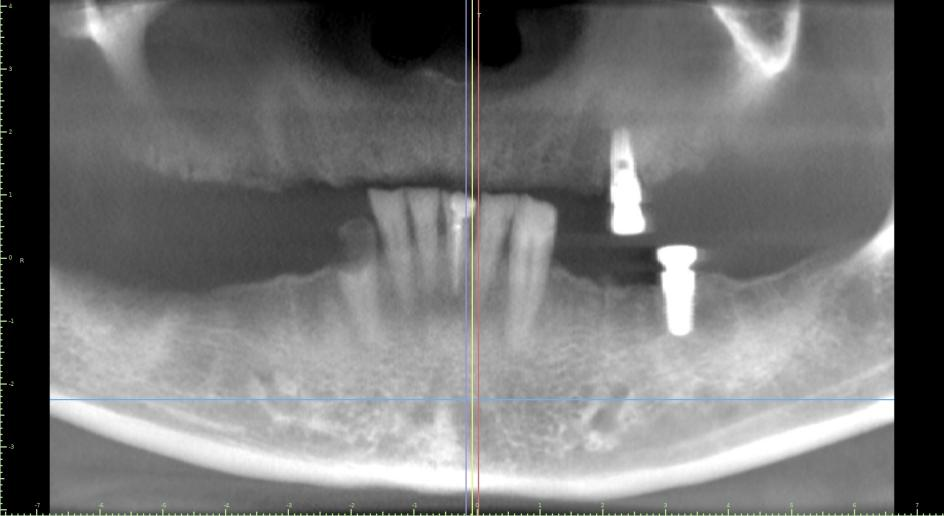

Figure 2 shows an x-ray result of the patients failing implants and overall teeth condition

After examining the patient's current condition, Dr. Glen confirmed the treatment plan of removing the remaining implants and existing teeth. Followed by placing 6 upper implants and 6 lower implants with 2nd-day delivery to minimize the wait time as much as possible before the final restorative plan of placing full-arch upper and lower dental implants. Dr. Glen was able to use the data collected by an intraoral scanner to create the design for full-arch upper and lower dental implants.